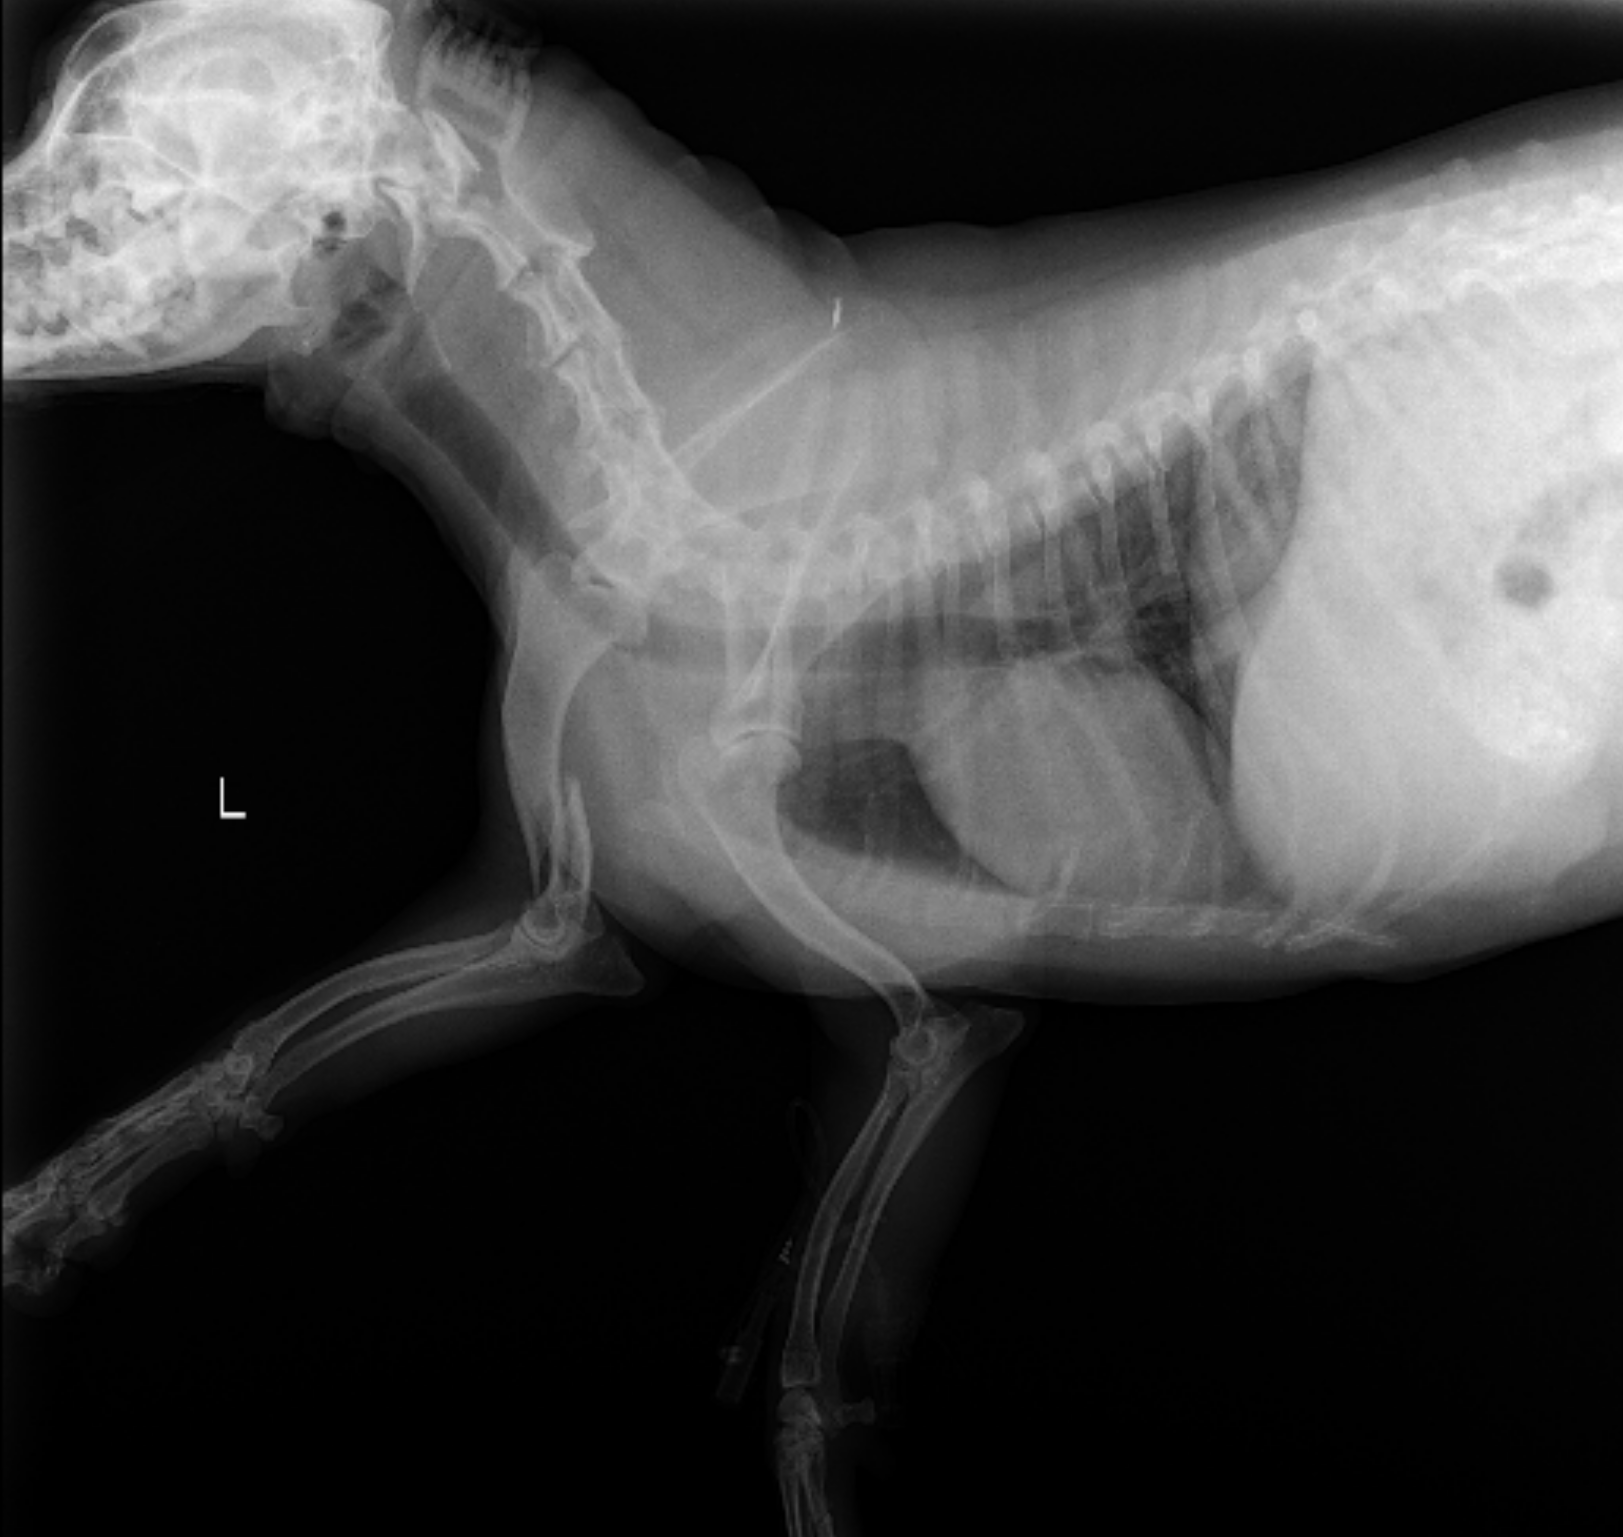

his right front humerus is broken.

Due to the location and severity of his injury,

he needs surgery to heal.